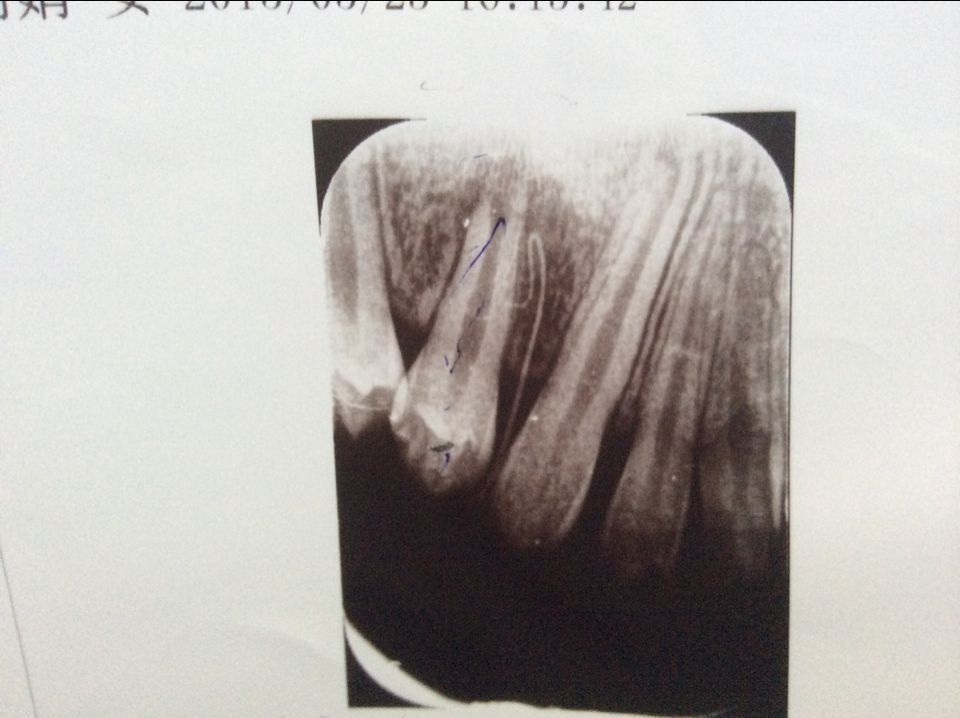

孩子10岁牙床脓肿,牙齿表面完好无黑斑 请问能不去神经吗,吃药脓肿能下去吗? 此图中长的线性是医生从脓肿处下的好像小棍的东东 点击展开 匿名用户 2015-05-24 21:37 推荐回答 您好,您小孩的牙齿是根尖发炎了,要做根管治疗,要去神经的。 匿名用户 2015-05-25 11:44 宝宝知道提示您:回答为网友贡献,仅供参考。 相关问题 您好医生,我家宝宝牙齿有黑斑,但是表面很平滑,没有任何不适,刚开始挨着牙床,慢慢 一岁半宝宝,牙齿有黑斑,牙齿发白怎么回事 我的宝宝牙齿怎么长黑斑了?牙齿怎么了 是不舒服还是什么呢